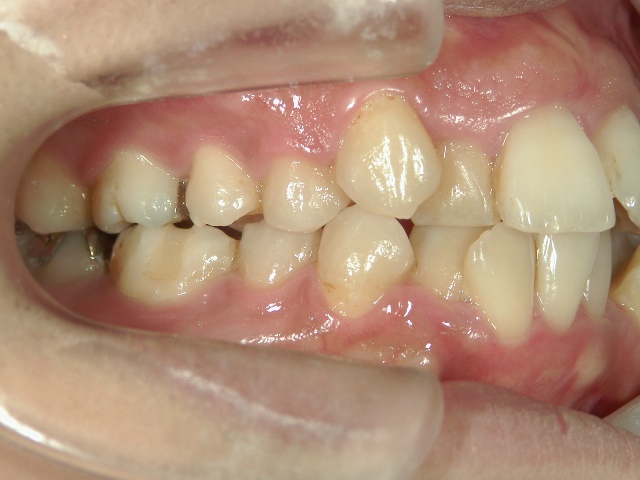

矯正歯科 治療前矯正歯科 治療前

矯正歯科 治療前 上下左右4番 計4本を抜歯して叢生を改善しました。

no.31_1962_治療前_右.JPGno.31_1962_治療前_正面.JPGno.31_1962_治療前_左.JPG